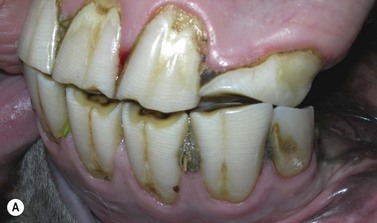

Fig. 8.6 (A) This skull radiograph shows absence of 306 (an intercurrent sclerotic, eruption cyst lies beneath the 307). (B) Intra-oral examination shows marked overgrowth of the opposing 206, with just a remnant of the deciduous tooth (706) visible in the intra-oral mirror. Such retention of deciduous teeth remnants is common in hypodontia, due to absence of pressure from an underlying erupting permanent CT to aid shedding.